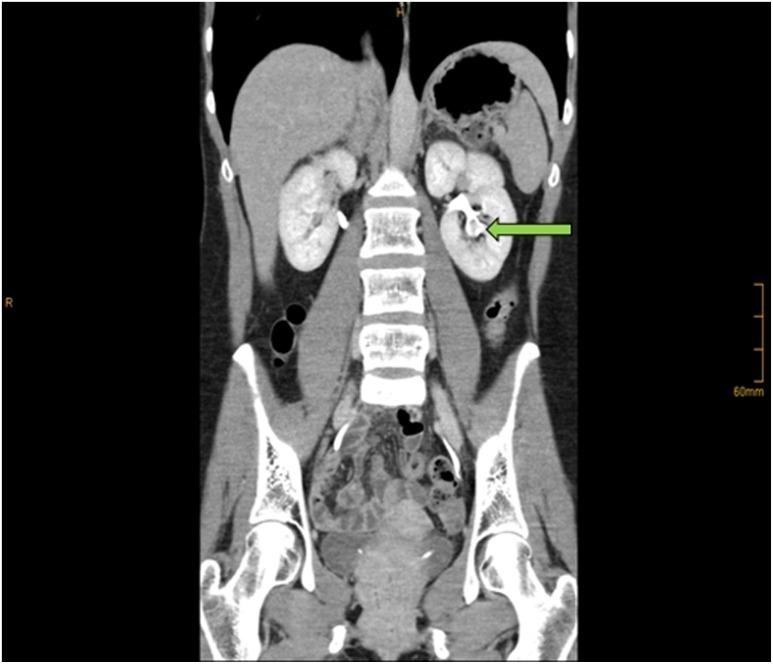

Asymptomatic microscopic hematuria (AMH) is incidentally found during routine health screenings. In the clinical evaluation of persistent AMH imaging modalities, CT urography, MR urography, and retrograde pyelography are of diagnostic importance. In case of pathologic findings (e.g., contrast-filling defects), endoscopic evaluation is mostly performed. To our knowledge, we report the first case of a patient with persistent AMH caused by biopsy-proven renal papillary hyperplasia.

无症状性镜下血尿(AMH)是在常规健康筛查中偶然发现的。在对持续性AMH进行临床评估时,CT尿路造影、磁共振尿路造影和逆行肾盂造影等影像学检查具有诊断意义。如果发现病理结果(如造影剂充盈缺损),大多会进行内镜评估。据我们所知,我们报告了首例经活检证实为肾乳头增生导致的持续性AMH患者。